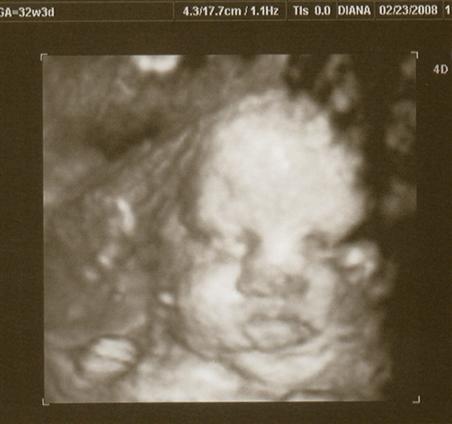

I had my 32 week growth sono on Saturday. Everything is looking good!

is roughly 4.5 - 4.75 pounds and measuring about 1-2 weeks ahead of my scheduled due date. She's in position and all looks good!

The tech took some 3D pics too!! Image Attachment(s):

Aaaaaaaaawww!! Love the one with the parted lips! Blowing kisses to you!!!